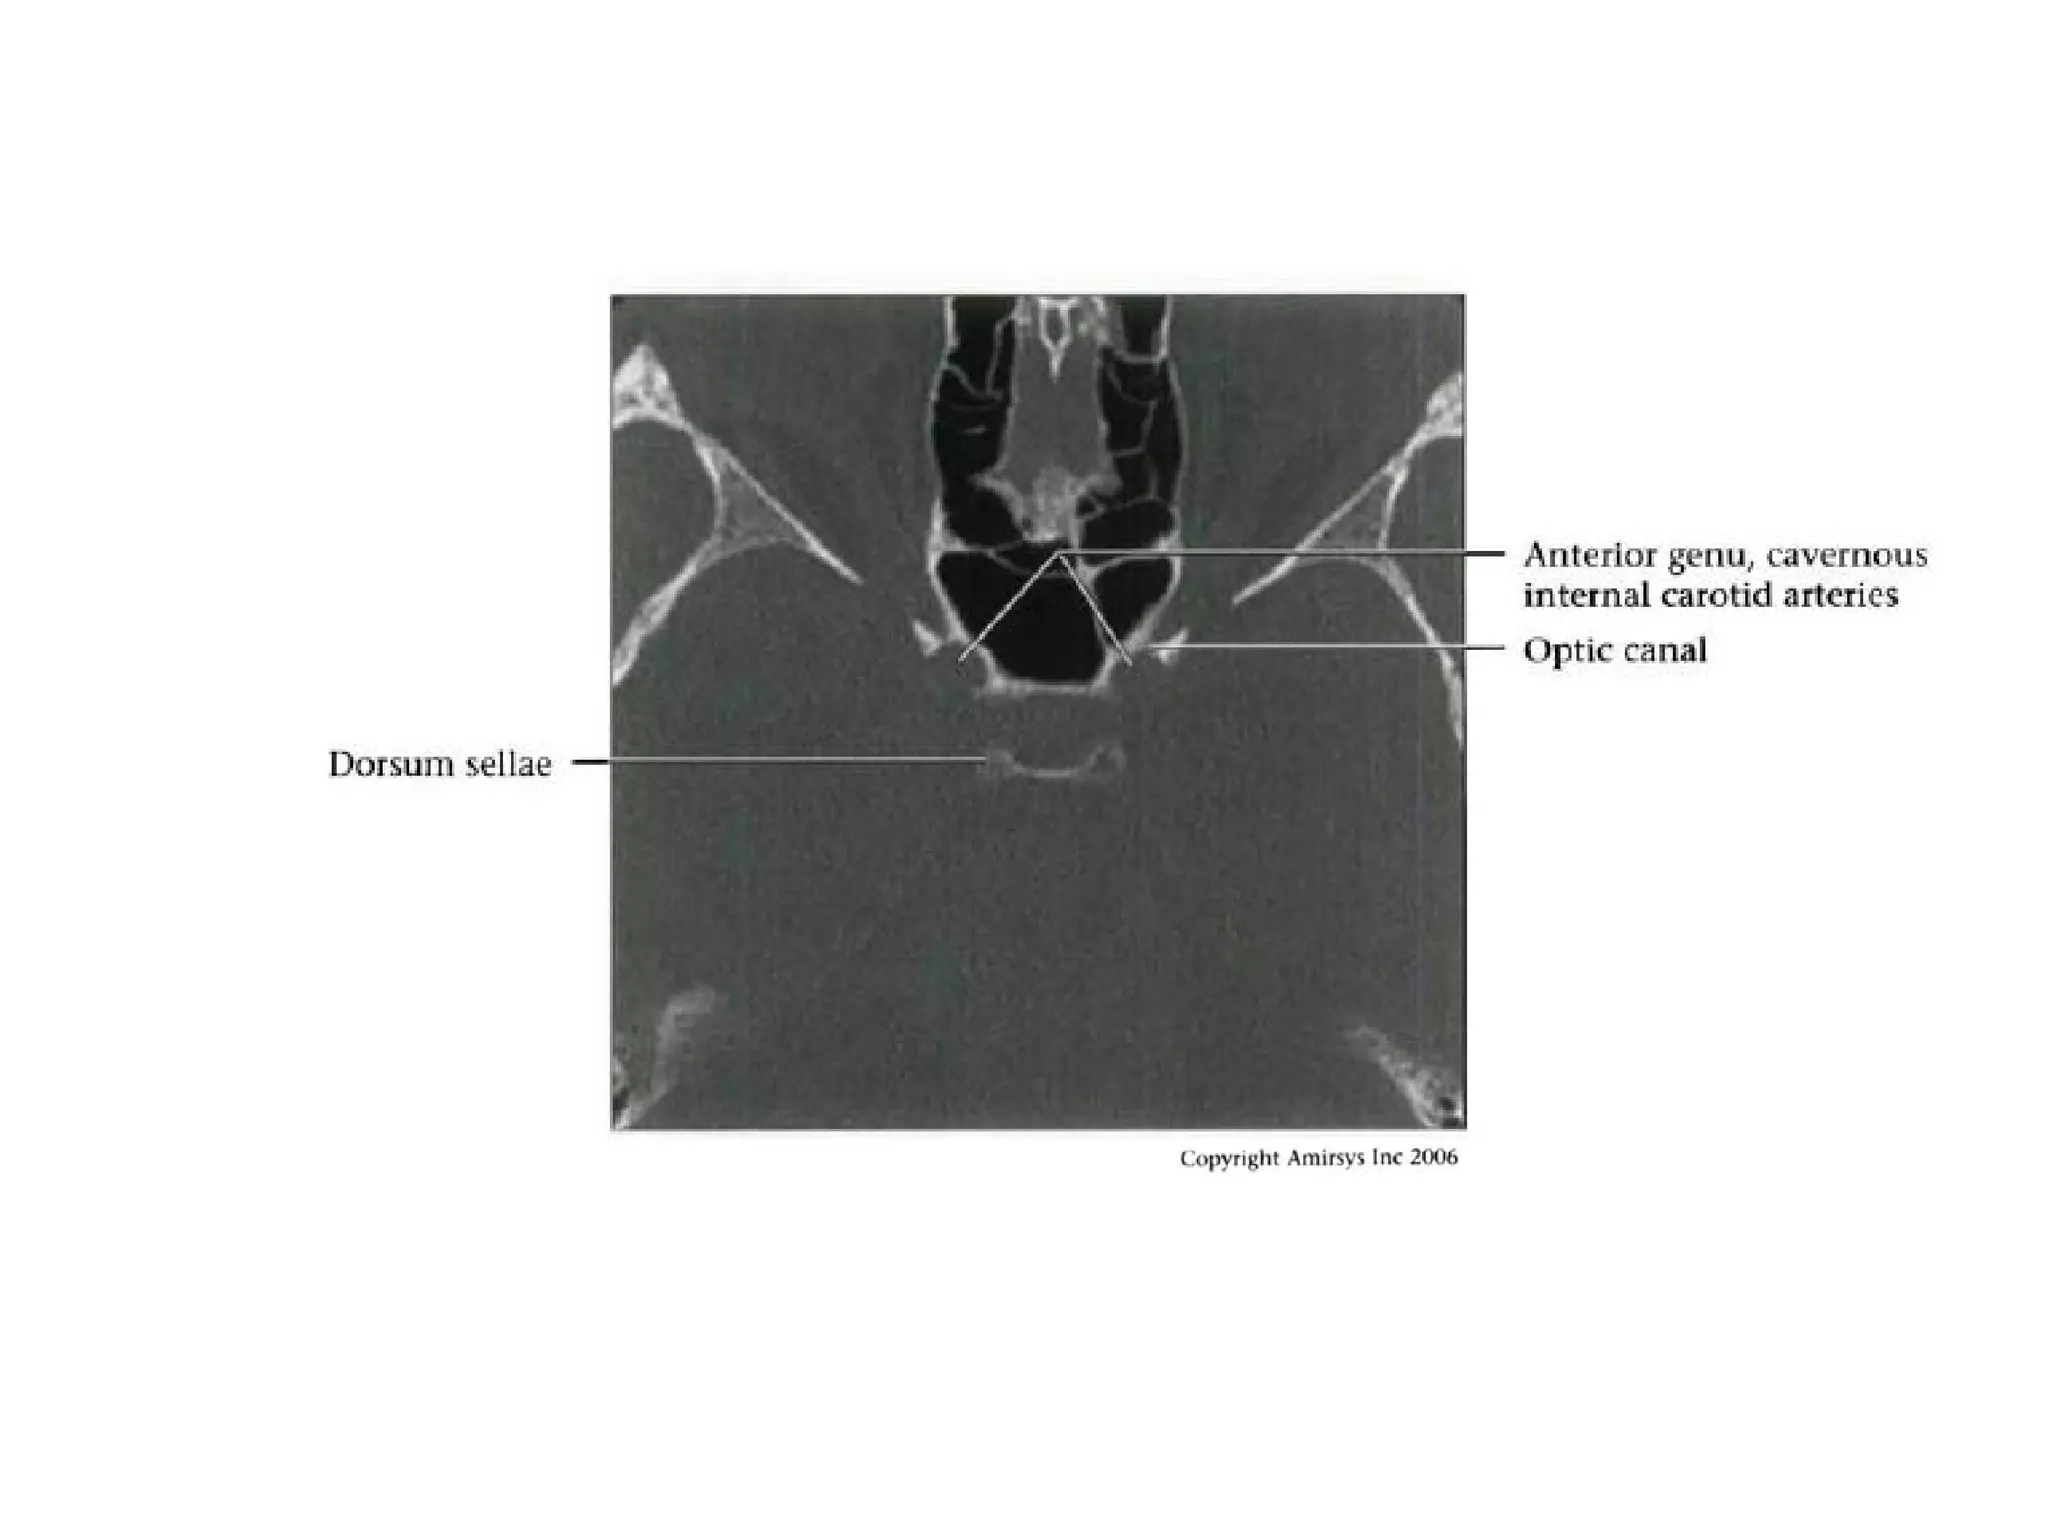

Cavernous (C4) segment

• Three subsegments joined by two genus (knees)

- Posterior vertical (ascending) portion

- Posterior (more medial) genu

- Horizontal segment

- Anterior (more lateral) genu

- Anterior vertical (subclinoid) segment

Clinoid (C5) segment

• Between proximal, distal dural rings of

cavernous sinus

• Ends as ICA enters subarachnoid space

near anterior clinoid process